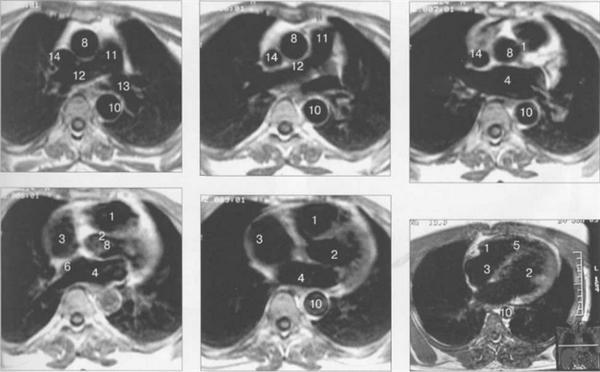

Рис. 9.47. МРТ сердца. Аксиальная плоскость.

Здесь и на рис. 9.48—9.52:

I — правый желудочек, 2 — левый желудочек, 3 — правое предсердие, 4 — левое предсердие, 5 — межжелудочковая перегородка, 6 — межпредсердная перегородка, 7 — задняя стенка левого желудочка, 8 — восходящая часть аорты, 9 — дуга аорты, 10 — нисходящая часть аорты, 11 — легочный ствол, 12 — правая легочная артерия. 13 — левая легочная артерия, 14 — верхняя полая вена, 15 — нижняя полая вена, 16 — трахея.

На рис. 9.47—9.52 представлены Т1-ВИ наиболее часто используемых МР-сечений сердца.